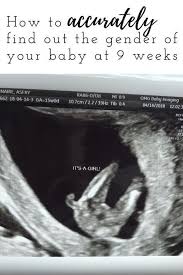

The chinese pregnancy calender is an ancient oriental tradition which can predict the sex of the baby before birth by simply combining values of the moon age of the mother at the time of conception and the lunar month in which the child was conceived. If you have a prenatal blood test nipt you may be able to find out your baby s sex as early as 11 weeks of pregnancy. Nipt results must be confirmed by a diagnostic test such as cvs or amniocentesis. Learning your baby s gender for real one accurate way to predict whether you re having a boy or girl is to have an ultrasound which is usually done between weeks 18 20 of pregnancy.

You can also find out the sex of your baby by having noninvasive prenatal testing nipt a blood test which is usually done between 11 and 14 weeks of pregnancy. Unfortunately it s not always possible to determine the gender of a baby via ultrasound. The process through which sex is determined is called human sexual differentiation. An ultrasound when you are between 15 and 22 weeks pregnant can also enable the technician or physician to identify your baby s gender because at this stage of pregnancy a number of signs may show clearly on the scan.

Ultrasounds may reveal sex organs by 14 weeks but they aren t considered fully accurate until 18 weeks.